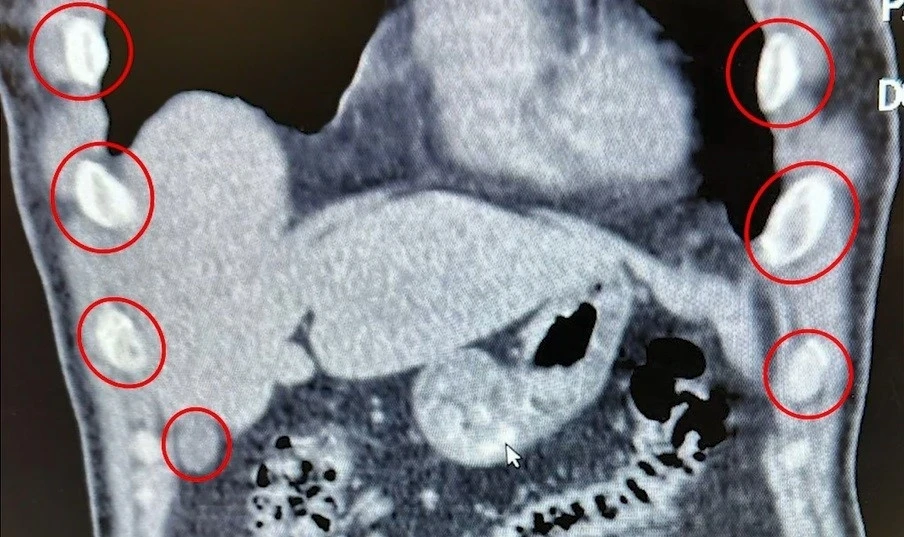

Bitlis İl Emniyet Müdürlüğü Narkotik Suçlarla Mücadele Şube Müdürlüğü ekipleri, uyuşturucu ile mücadele kapsamında önemli bir operasyona imza attı. Tatvan ilçesinde durdurulan bir otobüste yolcu olarak seyahat eden yabancı uyruklu 2 kişi gözaltına alındı. Şahısların yapılan tıbbi müdahalesinde, yuttukları 136 kapsül halinde toplam 1 kilo 48 gram metamfetamin ele geçirildi.